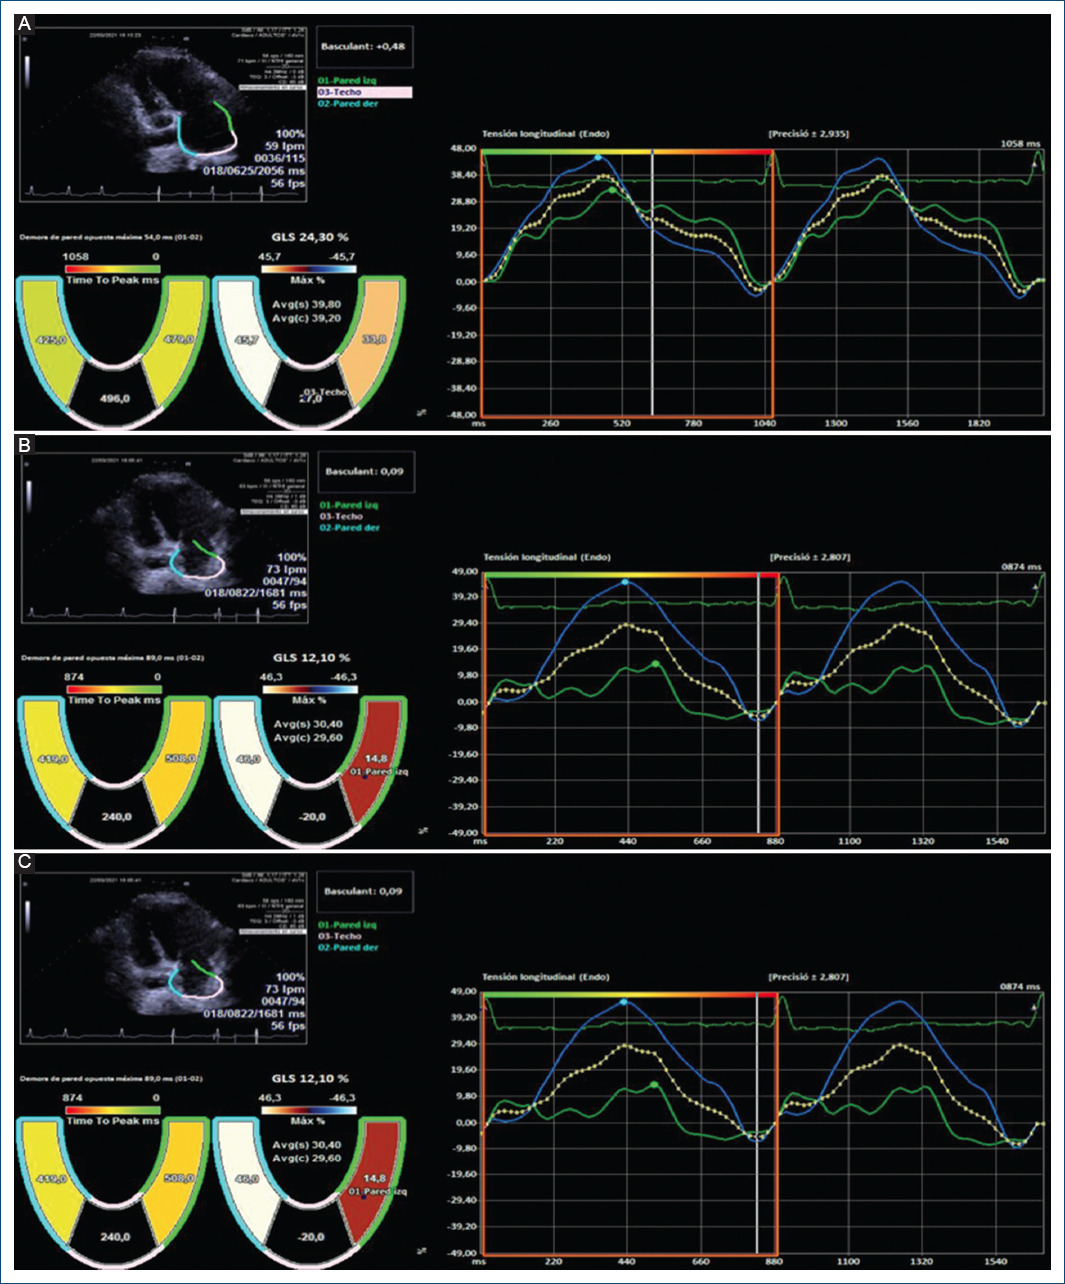

Intriguingly, in our study, we observed in a non-protocolized way some models of basal dyssynchrony and dynamic image sequences after an atrial extra systole that suggest different pathogenesis at the beginning of repetitive forms. Figure 1 suggest the origin of extra systole at the level of the pulmonary veins whose arrhythmogenic potential is classically defined and in addition, there is an anatomical alteration in intratrial conduction involving in some way the Bachmann’s fasciculus. This patient presented atrial fibrillation just before the ablation, during catheter manipulation and showed RUNs, and PAF in the follow-up Holters not seen in the initial analysis. Figure 2 show the initial sequences of extra systoles with changes in longitudinal and segmentary strain that guide on the functional state of the left atrium and its adaptation mechanisms.

Figure 2 75-year-old patient, hypertensive with atrial extrasystole bursts and no evidence of atrial fibrillation with an electrocardiograph P wave of 122 ms and an electrocardiogram which showed slight left atrial dilation (35 ml/m2) and no increase in the electromechanical conduction time with asynchrony in the longitudinal tension between the septal and lateral walls (54 ms, 5% relative to the RR). (A) shows the basal recording; (B) is during the extrasystole with a slight increase in the asynchrony and the global strain initiating a sequence of several recurrent beats; (C) shows an increase in the global and segmental reservoir causing the disappearance of the asynchrony and equalising the wall tension values without active contraction. This suggests a homogeneous activation front without anatomical obstacle, with increased atrial pressure and adaptive stretching of the atrial wall.